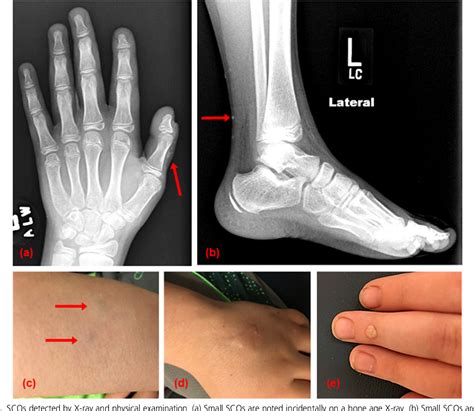

• Brachydactyly: Shortening of the bones in the hands and feet, particularly the fourth and fifth metacarpals and metatarsals.

• Subcutaneous Ossifications: These are small, hard lumps of bone that form under the skin, often in the hands, feet, and other areas.

• Clinical Evaluation: A thorough physical examination to assess the characteristic features of AHO, such as short stature, obesity, and brachydactyly.

• Orthopedic Interventions: Surgical procedures may be required to correct skeletal abnormalities, such as brachydactyly or subcutaneous ossifications.